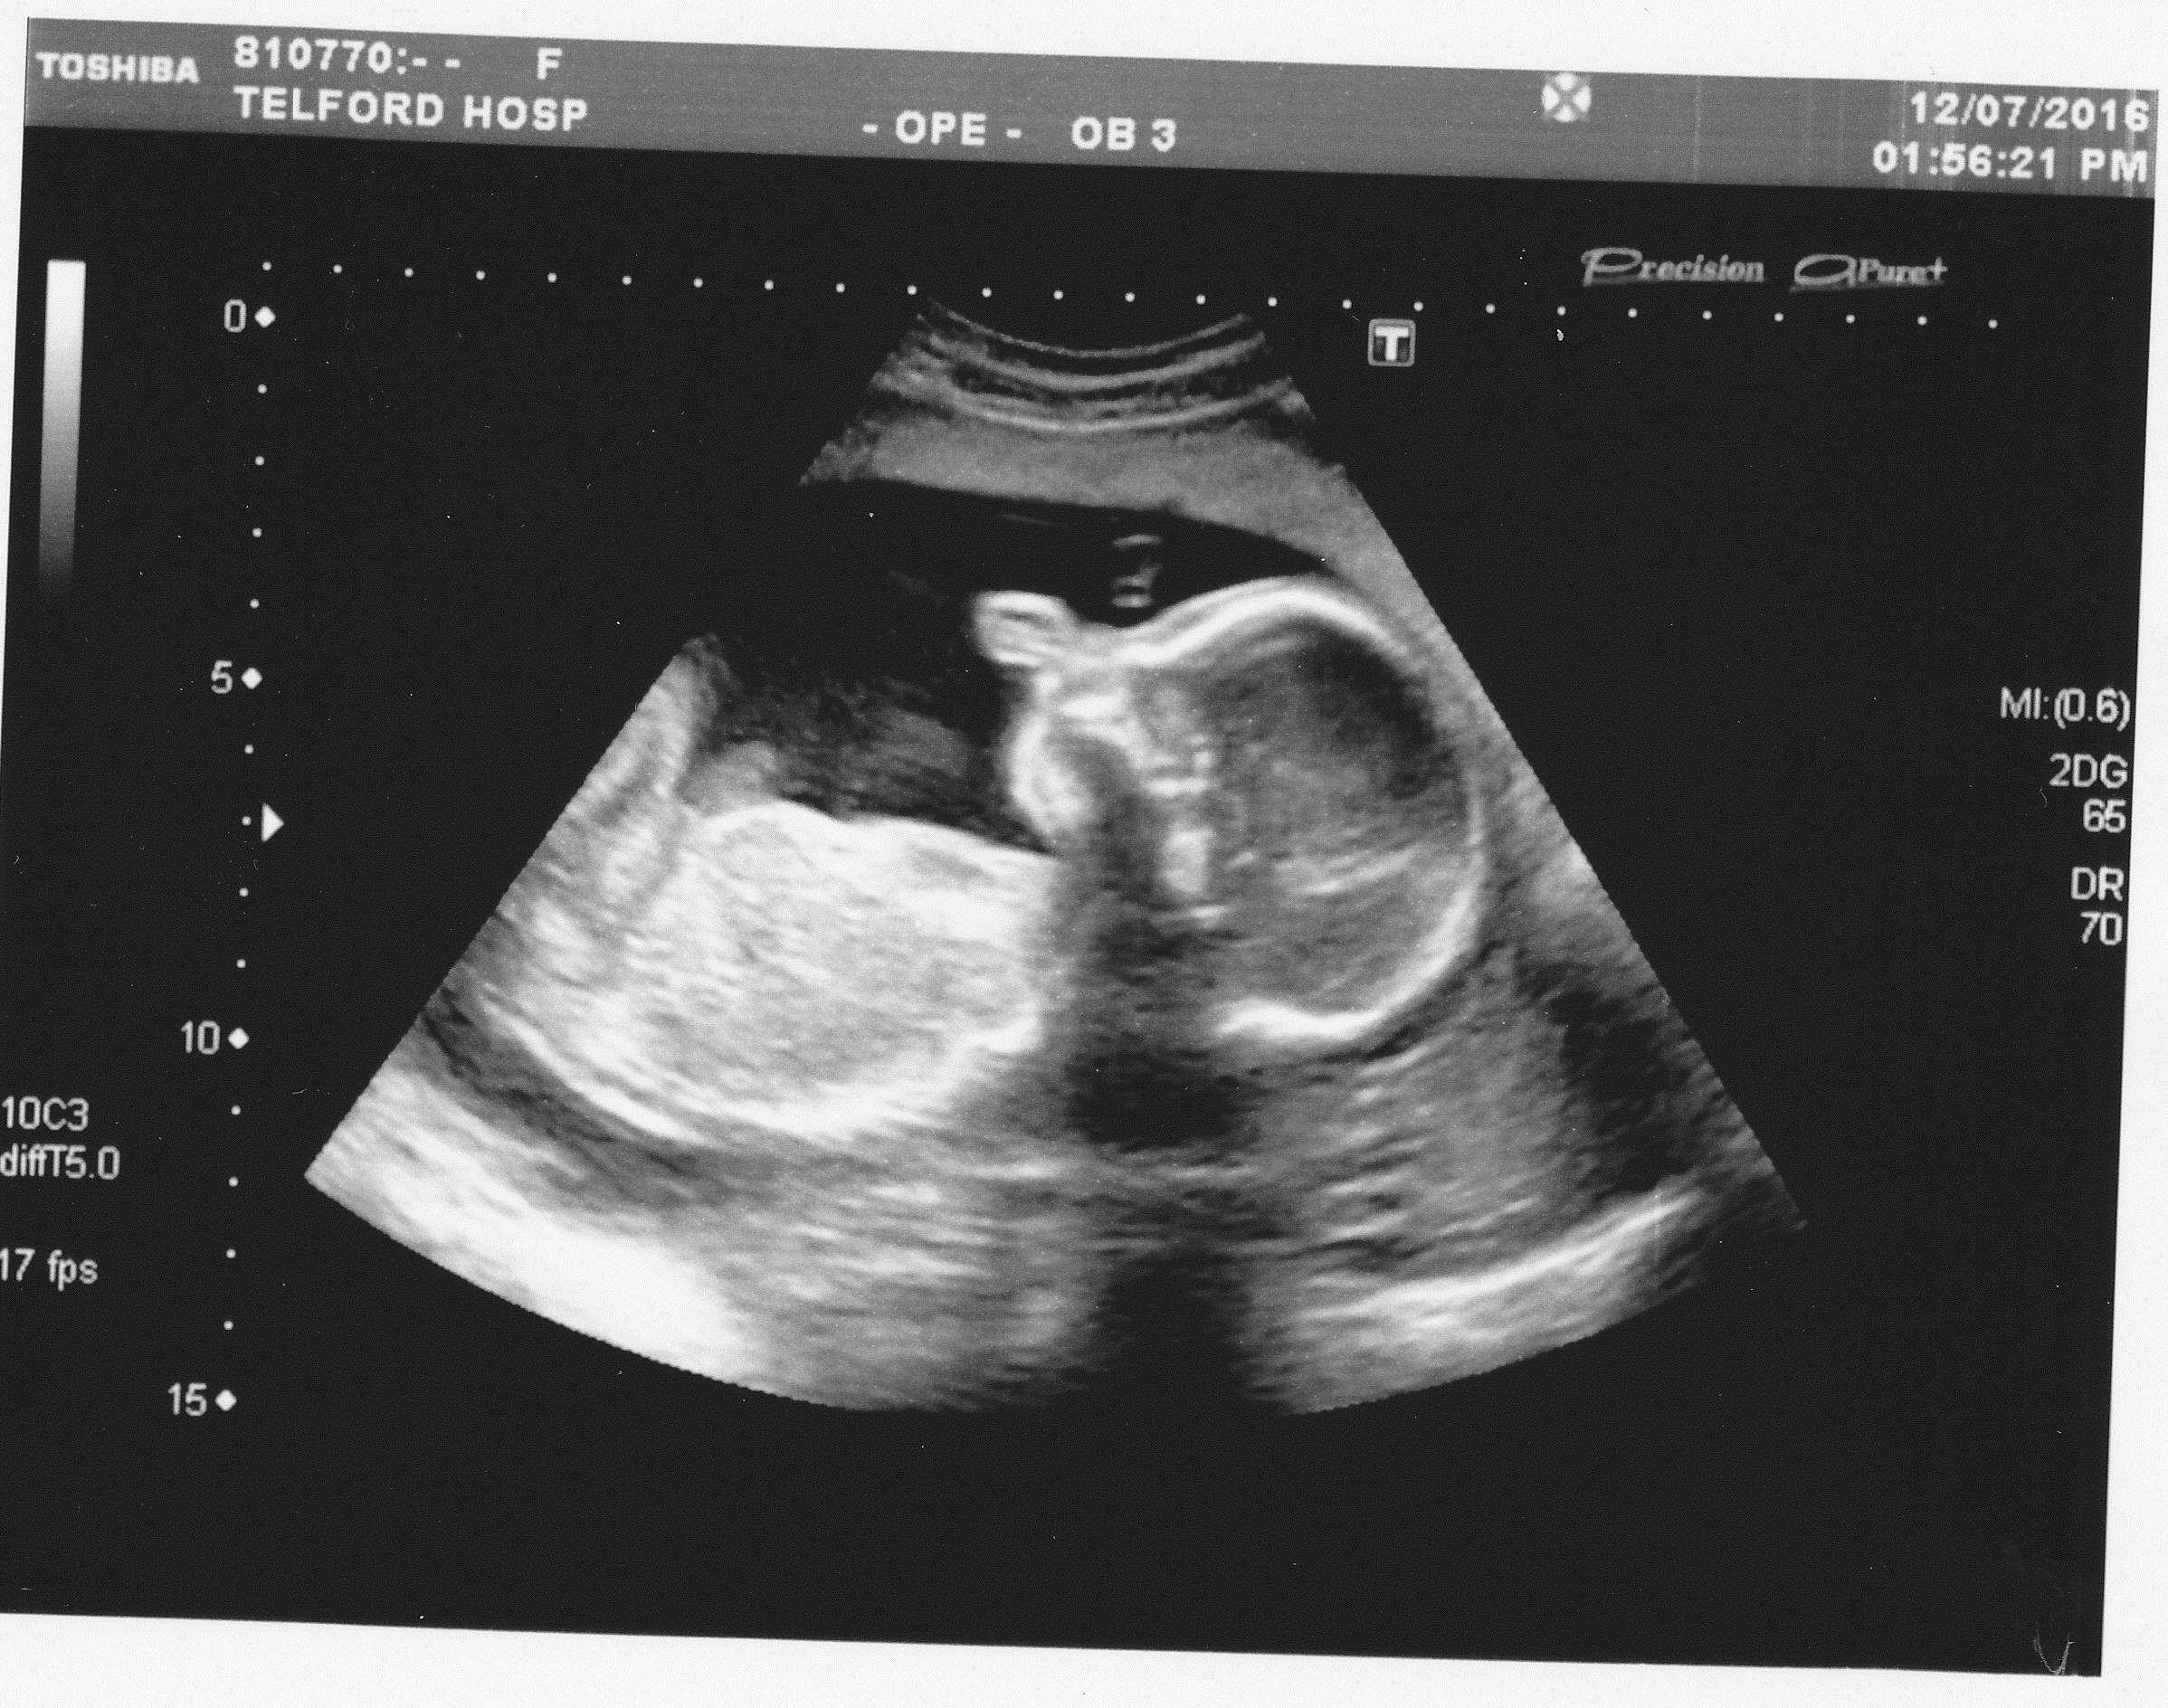

Attachment 32320

11 week scan above ^